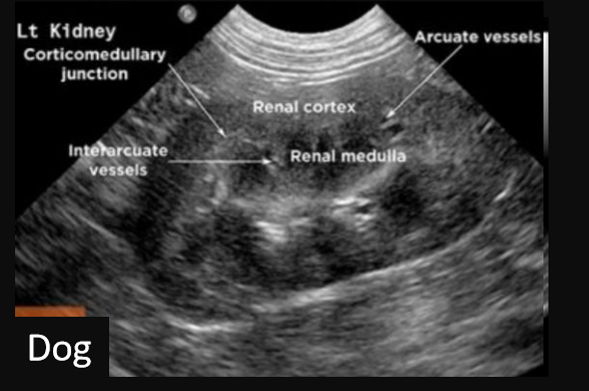

Label this frontal/dorsal kidney ultrasound

A

Label this frontal/dorsal view kidney ultrasound